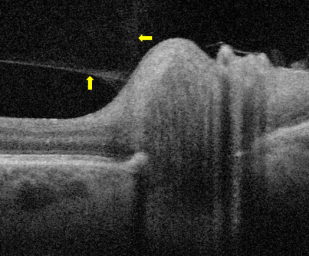

Optical coherence tomography

The presence of vitreopapillary traction was historically assessed by ophthalmoscopy and dilated slit lamp microscopy. Advanced non-invasive imaging techniques such as OCT have allowed for better morphologic characterization of the posterior hyaloid, retina and vitreopapillary interface. In vitreopapillary adhesion and traction, OCT findings may include optic disc elevation, retinal nerve fiber layer thickening, PVD with a thickened, hyperreflective posterior hyaloid attached to the optic disc or optic disc margin.[3][11][13]